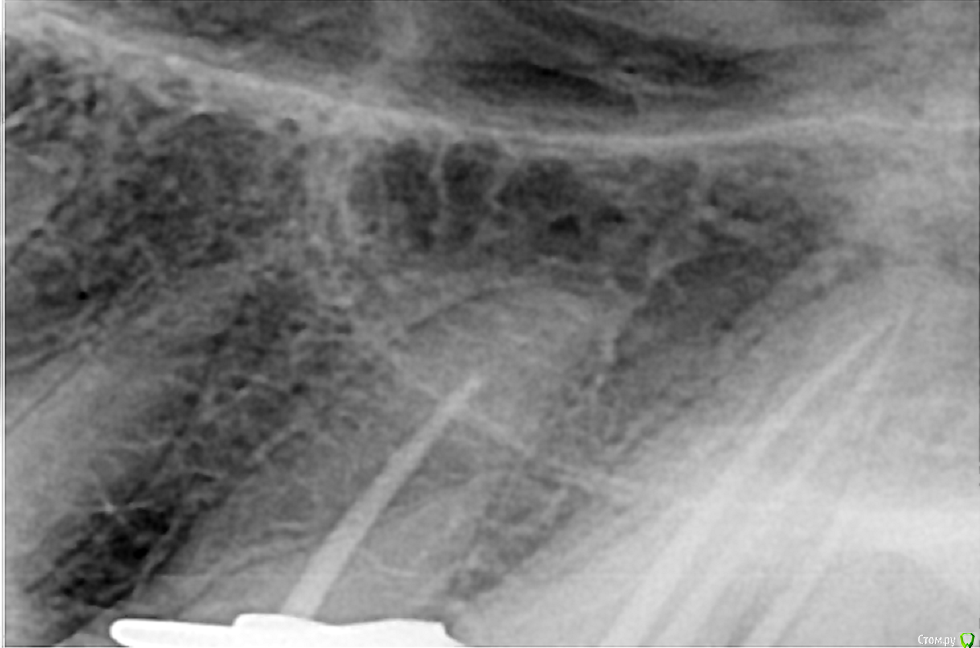

Всем доброго дня! В коем то веке появилась свободная минутка и решил поделиться с вами несколькими кейсами. Обострение хронического периодонтита 27, каналонаполнитель в нёбном канале. Коффердам, извлечение каналонаполнителя, хлорка, лимонка, УЗ, кальций. Обтурация Ah+ латеральная компакция.